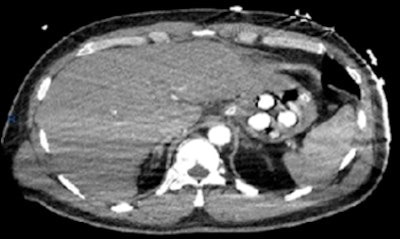

In one case, a 43-year-old man presented with an out of hospital cardiac arrest upon arrival at the airport. After being transferred to A&E, he was resuscitated and a CT pulmonary angiogram was performed to exclude a pulmonary embolism. No embolism was demonstrated, but four well-defined radiopaque densities (~300 Hounsfield units) were identified in the stomach.

"Gastroscopy was subsequently performed, which confirmed four white pill-shaped packets," the researchers recalled. "Two empty bags from burst packaging were removed. One of the foreign objects was removed with a two-prong balloon grasper."

The patient then underwent laparotomy for surgical removal of three packets from the fundus of the stomach. Unfortunately, the patient was unable to recover and died, and a toxicology screen confirmed the presence of cocaine.